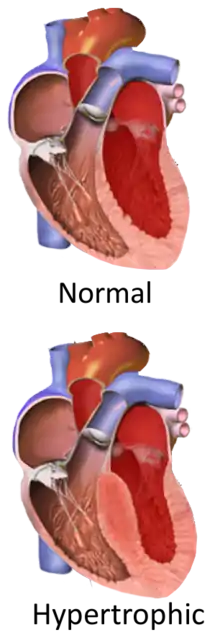

Hypertrophic cardiomyopathy (HCM, or HOCM when obstructive) is a condition in which muscle tissues of the heart become thickened without an obvious cause.[8] The parts of the heart most commonly affected are the interventricular septum and the ventricles.[10] This results in the heart being less able to pump blood effectively and also may cause electrical conduction problems.[3] Specifically, within the bundle branches that conduct impulses through the interventricular septum and into the Purkinje fibers, as these are responsible for the depolarization of contractile cells of both ventricles.[11]

Depending on whether the distortion of normal heart anatomy causes an obstruction of the outflow of blood from the left ventricle of the heart, HCM can be classified as obstructive or non-obstructive.[35] The obstructive variant of HCM is hypertrophic obstructive cardiomyopathy (HOCM), also historically known as idiopathic hypertrophic subaortic stenosis (IHSS) or asymmetric septal hypertrophy (ASH).[36] The diagnosis of left ventricular outflow tract obstruction is usually made by echocardiographic assessment and is defined as a peak left ventricular outflow tract gradient of ≥ 30 mmHg.[37]